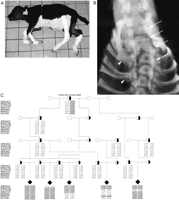

Detailed clinical characterization of CVM demonstrated a composite phenotype with axial skeletal deformities such as hemivertebrae, misshaped vertebrae, ankylosis of mainly the cervico-thoracic vertebrae, scoliosis, and symmetric arthrogryposis of the lower limb joints, craniofacial dysmorphism, as well as cardiac anomalies (Agerholm et al. 2001, 2004; Nielsen et al. 2003) (Fig. 1A,B). The diagnosis of CVM can be difficult to make because of significant clinical heterogeneity among affected calves and the occurrence of phenocopies. A presumptive diagnosis can usually be obtained at necropsy in combination with pedigree information; however, a definitive diagnosis requires DNA testing (Agerholm et al. 2004). The vertebrate axial skeleton is derived from somites generated by segmentation of the paraxial mesoderm in an intricate process that requires participation of two signal-transduction pathways, Wnt and Notch (Pourquie 2003; Aulehla and Herrmann 2004). Thus, somitogenesis involves a molecular oscillator mechanism consisting of cyclic expression of genes encoding several Notch pathway components such as the glycosyltransferase Lunatic Fringe, Notch ligands, downstream target genes of Notch as well as the Wnt pathway regulator Axin2. Moreover, morphogen gradients of Fgf8 (Dubrulle and Pourquie 2004) and Wnt3a (Aulehla et al. 2003) in the presomitic mesoderm are crucial for determining the position of somitic boundaries. Furthermore, somites differentiate into vertebrae, each having a unique morphological identity that depends on its position along the body axis. The axial identity of the vertebrae is specified by expression of an appropriate set of HOX genes in a coordinated fashion with the segmentation oscillator (Dubrulle et al. 2001; Zakany et al. 2001).

Complex vertebral malformation. (A) Affected calf. Notice the short neck and contraction of the distal joints. (B) Radiograph of the cervico-thoracic part of the vertebral column (arch removed), showing multiple malformed vertebrae and scoliosis (arrows) and fusion of the proximal part of several ribs (arrowheads), ventro-dorsal projection. (C) Pedigree and haplotype analysis. All affected calves can be traced back to a common ancestor Carlin-M Ivanhoe Bell. Genotypes of seven polymorphic makers at the disease locus on BTA3 that helped to define the disease locus are shown. The combined genotyping results suggested that the disease gene is located near BMS2790 in an ∼5 cM region flanked by the markers INRA003 and ILSTS029. The shared disease-associated haplotype is shaded in gray. (Filled symbols) Affected; (open symbols) unaffected; (half-filled symbols) carrier.

Genetic mapping of the disease gene

Affected animals are expected to be homozygous in polymorphic markers flanking the disease locus, as all chromosomes carrying the causative mutation descended from a common founder bull (Agerholm et al. 2001). Therefore, we performed a genome-wide scan for regions identical-by-descent. Seven calves diagnosed with CVM based on post-mortem examination as described (Agerholm et al. 2001) plus their parents were used in the initial genome scan using a panel of 194 microsatellite markers covering all 29 autosomes with pairwise distances between 10 and 20 cM. The results revealed that all seven calves were homozygous for the same allele of marker INRA003 (59.4 cM), whereas five calves had identical alleles in an adjacent marker HUJ246 (67.9 cM) on BTA3. To confirm this observation and to more accurately define the disease locus, we expanded the analysis with additional affected calves sampled by the Danish surveillance program for genetic defects to include a total of 30 affected calves plus available parental animals, which were genotyped with an increased marker density in the interval between INRA003 and HUJ246 (Fig. 1C). The evidence for linkage was highly significant with two-point lod scores of 8.13 (θ = 0.00) for BMS2790 (62.4 cM), 7.53 (θ = 0.00) for INRA003 (59.4 cM), and 5.12 (θ = 0.04) for ILSTS029 (64.9 cM). Haplotype analysis of the five-generation pedigree shown in Figure 1C revealed several critical recombinants that allowed us to narrow down the position of the disease gene. Thus, all affected calves were homozygous in BMS2790, and recombination between BMS2790 and the nearby markers INRA003 and ILSTS029 defined the limits of the CVM disease locus.